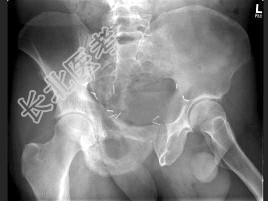

- 单项选择题男,56岁, 右髋部疼痛,5年前被确诊为前列腺癌, 结合图像,最可能的诊断是 ( )

A、骨纤维异常增殖症

B、转移性骨肿瘤

C、畸形性骨炎

D、内生软骨瘤

E、非骨化性纤维瘤